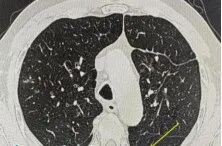

更让人意外的是,张大爷并不是我们通常认为容易感染这种病菌的免疫力低下患者,他的身体状况相对良好,免疫功能正常,却感染了这种素有“致命杀手”之称的真菌。那么什么是马尔尼菲篮状菌病?这种真菌感染的症状往往很隐蔽,患者多表现为咳嗽、咳痰、胸痛,很容易被当作普通的肺炎或咽喉炎来处理。肺部影像学也缺乏特征性改变,多类似于肺炎、肺结核或肺脓肿病变。正是因为这些症状、检查缺乏特异性,很多患者像张大爷一样,在确诊前经历了漫长的求医过程。如何预防和应对?诊断有一定难度可完全治愈如果您在竹林附近居住或工作,可能接触过竹鼠等野生动物,或在流行地区居住或旅行,那么您就属于这种疾病的高危人群。